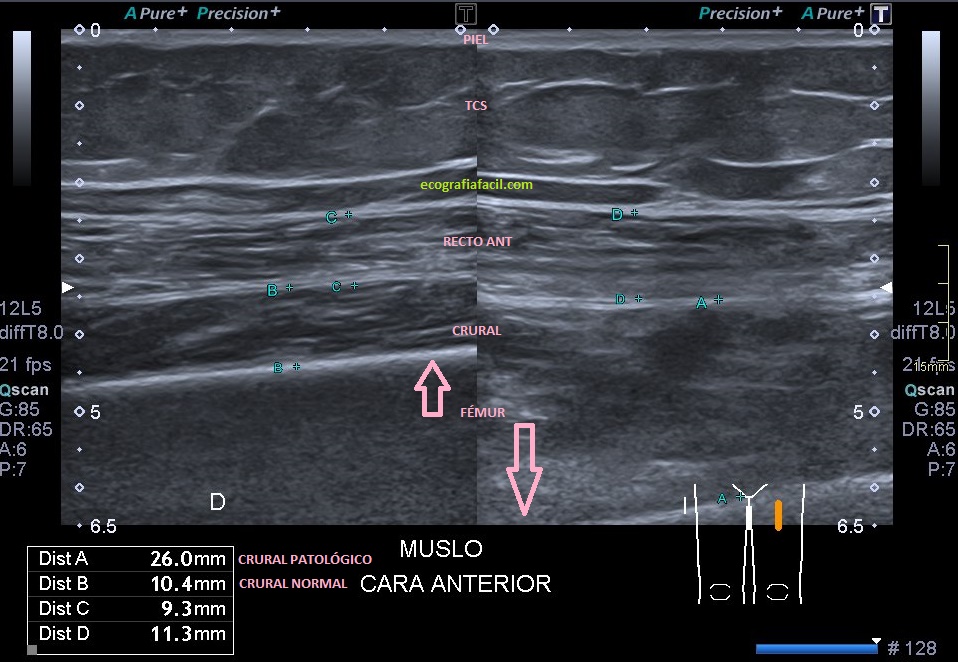

En la ecografía lo primero que veo al realizar la exploración en el corte axial del tercio medio es una llamativa diferencia de la ecoarquitectura del tercio medio del fémur afectado. En este caso lo que se observa a ojo de buen cubero es aumento del volumen antero posterior del Músculo Crural con respecto al Recto Anterior. Ese aumento de calibre es en todo el recorrido del fémur anterior, con lo que la afectación es desde proximal a distal del músculo citado anteriormente.

In ultrasound, the first thing I see when performing the exploration in the axial section of the middle third is a striking difference of the ecoarchitecture of the middle third of the affected femur. In this case, what is observed an increase in the anteriorvolume of the Crural Muscle with respect to the Anterior Rectus. This increase in caliber is throughout the course of the anterior femur, with which the affectation is from proximal to distal of the muscle previously spoken.

En la primera imagen encuentro ya los cambios referidos en el párrafo anterior. Inmediatamente en la imagen 2, comparativa de ambas estructuras, patológica y normal.La imagen 3 es una imagen correlacionada de RM, potenciada en T1 para que veas el mismo corte con dos técnicas diferentes, ambas en corte axial.

En la imagen 4, corte longitudinal de la estructura tanto en el lado patológico como en el lado contralateral normal.